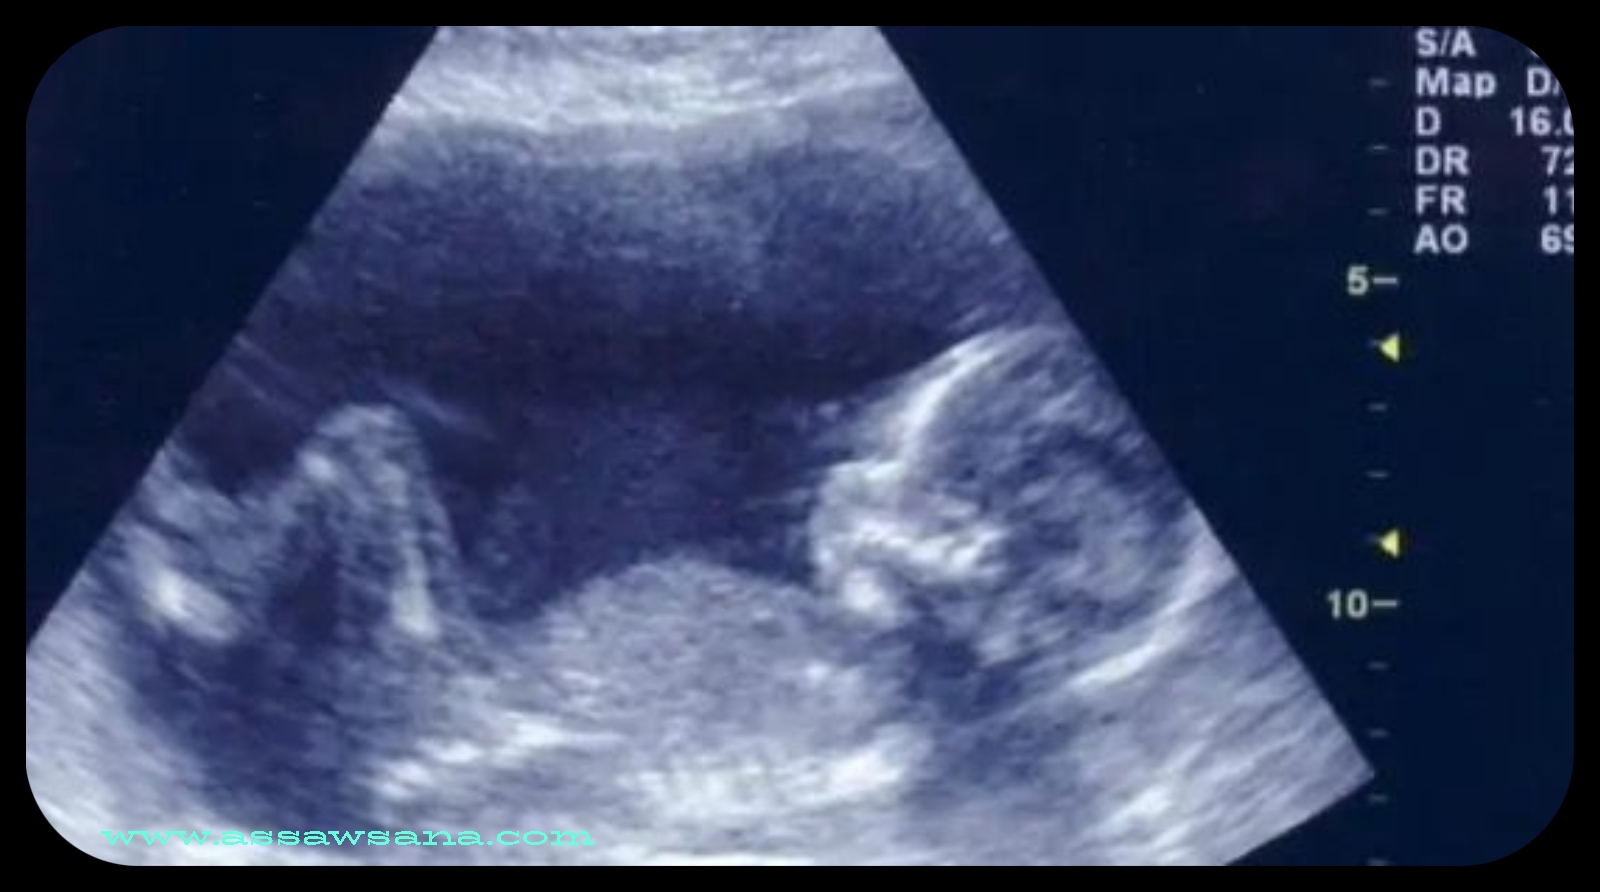

مظهر الجنين في الشهر الرابع

السوسنة- في الشهر الرابع من الحمل، يكون الجنين في مرحلة تطور ملحوظة، حيث تتشكل ملامح وجهه وتصبح أطرافه واضحة. تبدأ أعضاؤه الداخلية في العمل، ويظهر بشكل أكثر نضجاً، مما يعكس تحسناً في نموه واستعداده للحياة خارج الرحم.

يمتد الشهر الرابع من بداية الأسبوع الرابع عشر إلى نهاية الأسبوع السابع عشر من الحمل. ونبين فيما يأتي كيفية تغير شكل الجنين خلال هذه الأسابيع بشيءٍ من التفصيل: